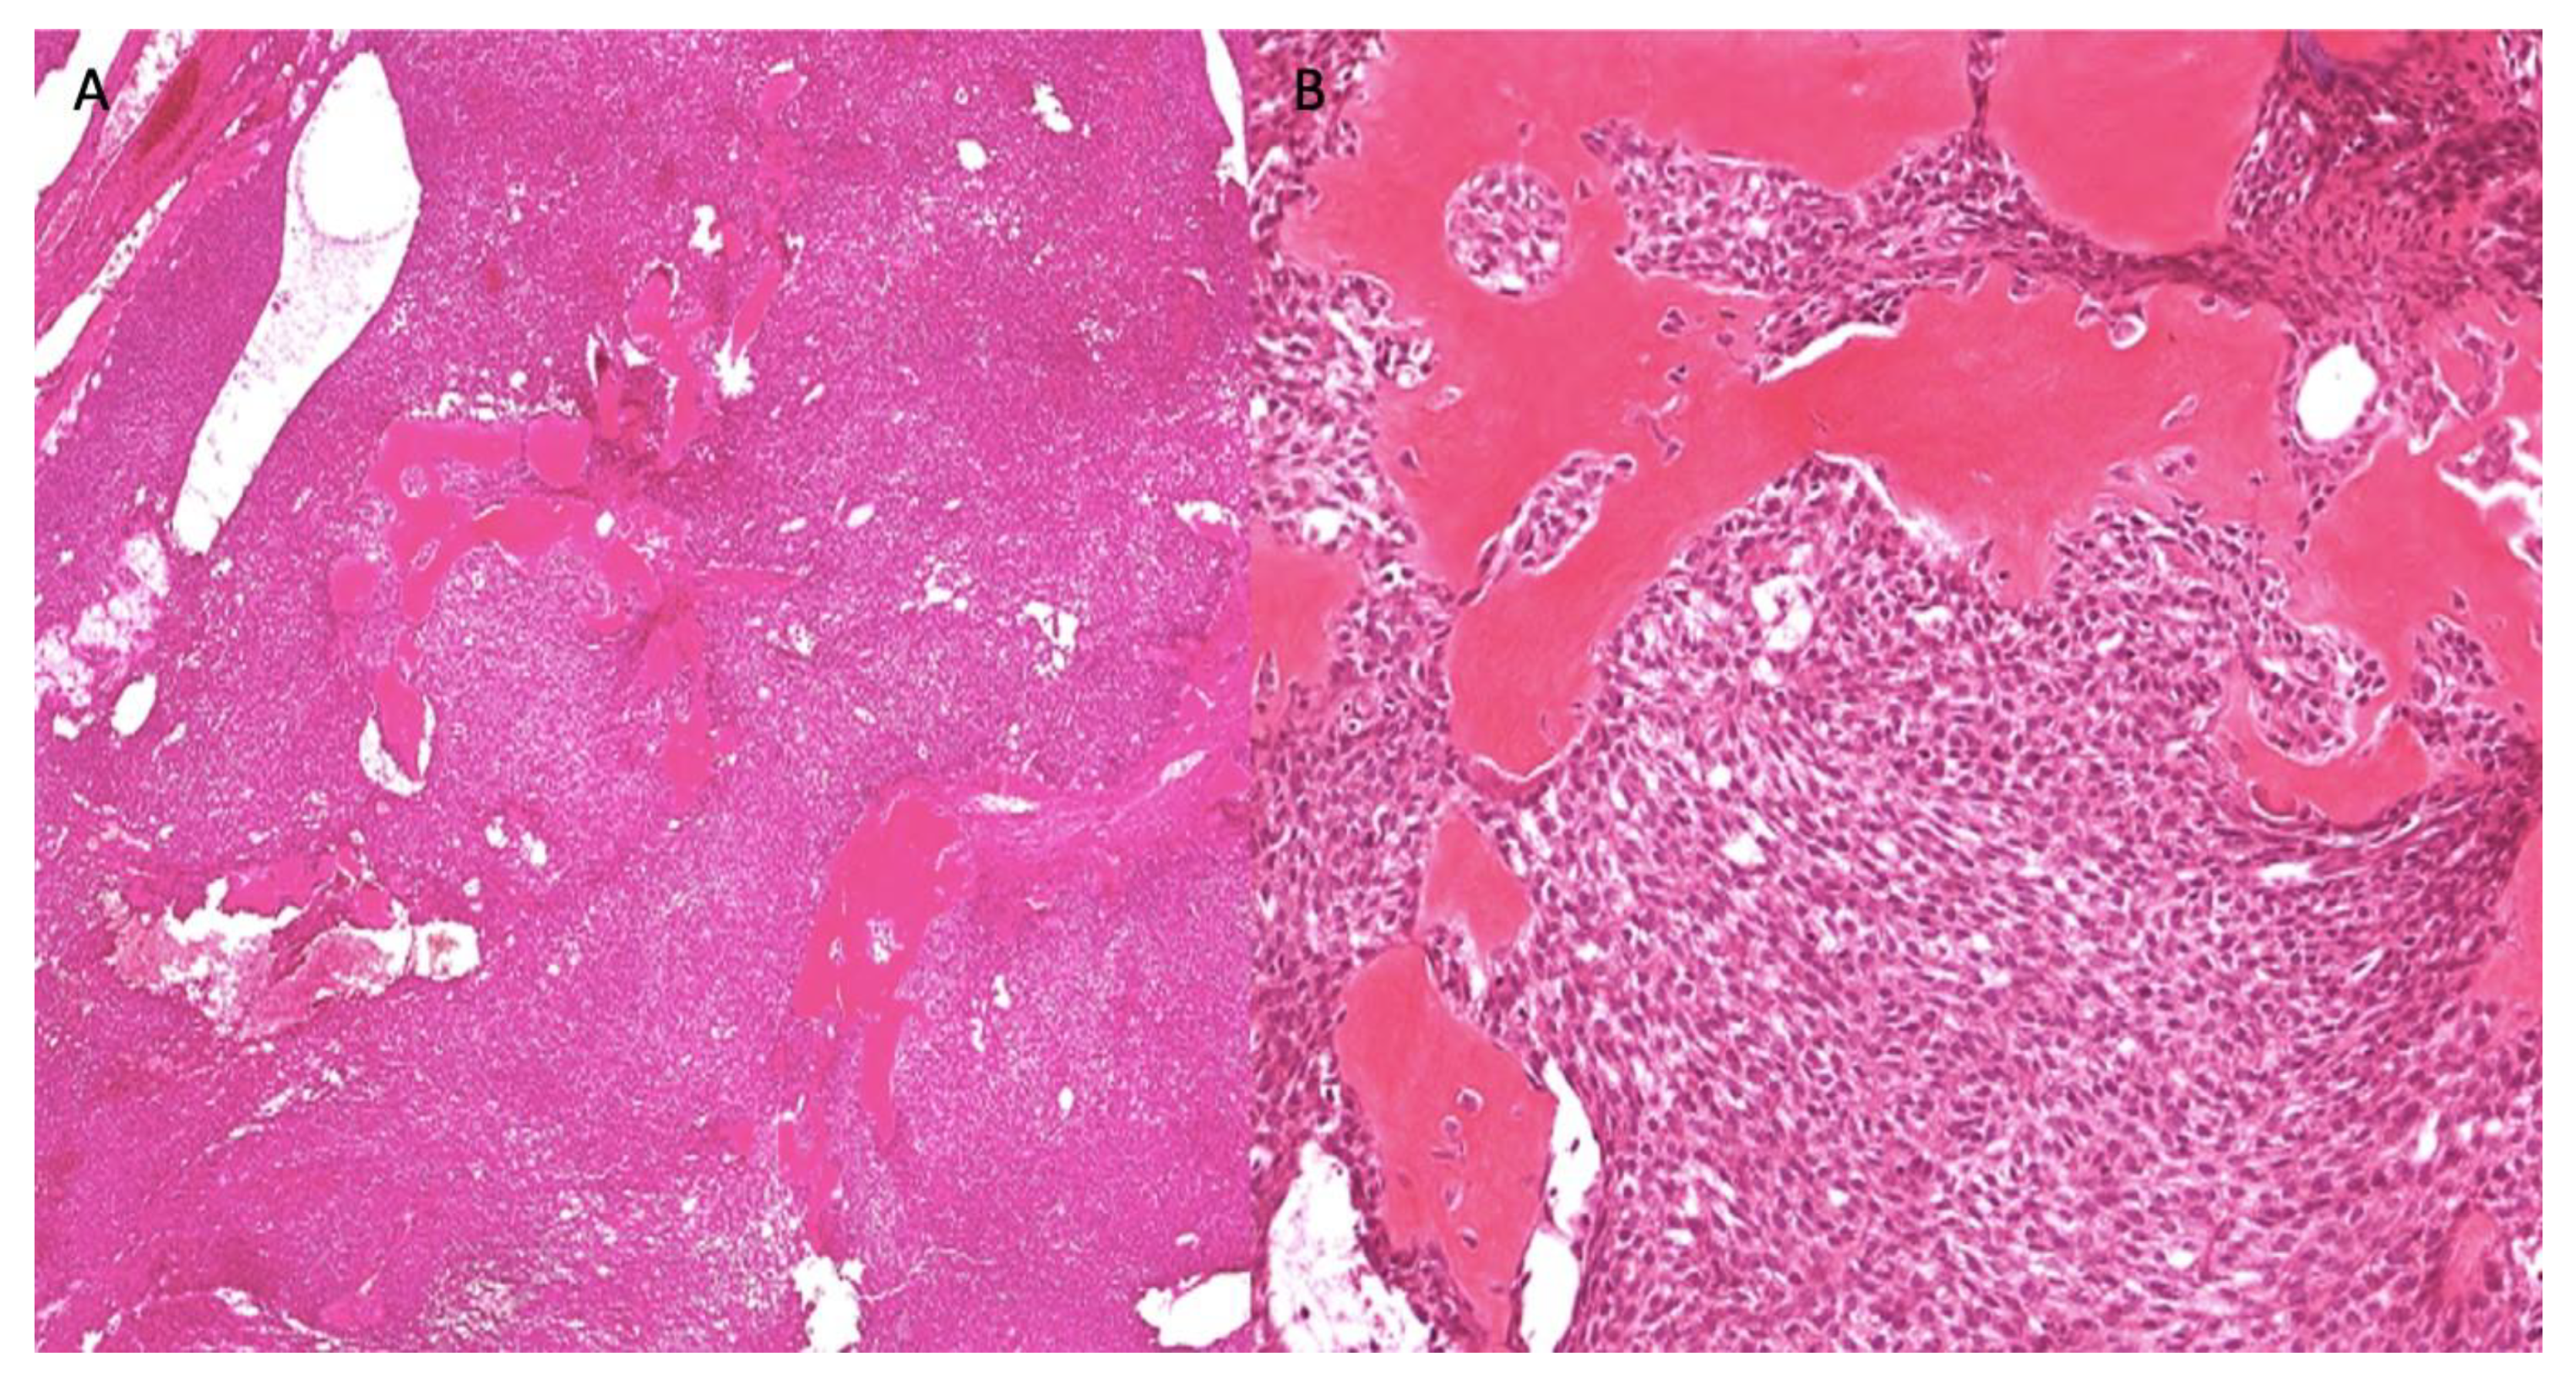

2.3. Case 3

| Staining/IHC | PAS (+) D-labile Mucicarmine (−), p63 (+) CK5/6 (+), CK19 (+) | PAS (+) D-labile Mucicarmine (−) CK5/6 (+) | H&E only |

| Morphology | Infiltrative, non-encapsulated malignant neoplastic odontogenic epithelial proliferation with clear cell component in a dense fibrous connective tissue stroma. Neoplastic cells arranged in anastomosing trabeculae. Nuclear hyperchromasia and pleomorphism surrounded by clear, vacuolated cytoplasm. Stroma was hyalinized, densely collagenized, hypocellular, and hypovascular. | Neoplastic odontogenic epithelial proliferation diffusely infiltrated the connective tissue stroma. Neoplastic cells arranged in islands of variable size, trabeculae, and nests. Nuclei were hyperchromatic, central, and pleomorphic surrounded by clear cytoplasm. | Infiltrative odontogenic epithelial neoplasm intermixed with eosinophilic dentinoid matrix. Neoplastic cells arranged in infiltrative, non-encapsulated sheets, cords, and nests of polygonal cells with central hyperchromatic and slightly pleomorphic nuclei surrounded by clear cytoplasm and occasional pale eosinophilic cytoplasm. Occasional mitotic figures were noted. Neoplastic epithelial sheets and cords blended with eosinophilic cellular matrix without cellular rimming consistent with dentinoid deposits. |

| Procedure | Right maxillectomy with negative margins | Left mandibulectomy Right temporomandibular joint arthroplasty Left fibula free flap | Right maxillectomy without orbital exenteration Right selective neck dissection Forearm free flap Four months adjuvant radiation |